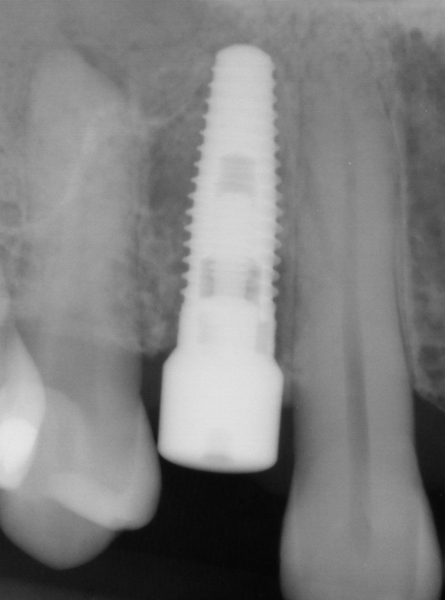

Fig 3. Placement of abutments that create blanching of the peri-implant soft tissue will result in unpredictable remodeling of the tissue to a more apical position, which may create an esthetically displeasing result. This is best managed in the esthetic zone by shaping the soft tissue in the provisional stage rather than with the definitive abutment.

Figure 3

Fig 4. Flared abutments (healing or definitive) that encroach on the biologic width of the peri-implant bone will also result in apical remodeling. This is likely to compromise the critical crest of bone on the adjacent teeth that is largely responsible for supporting the papilla.

Figure 4